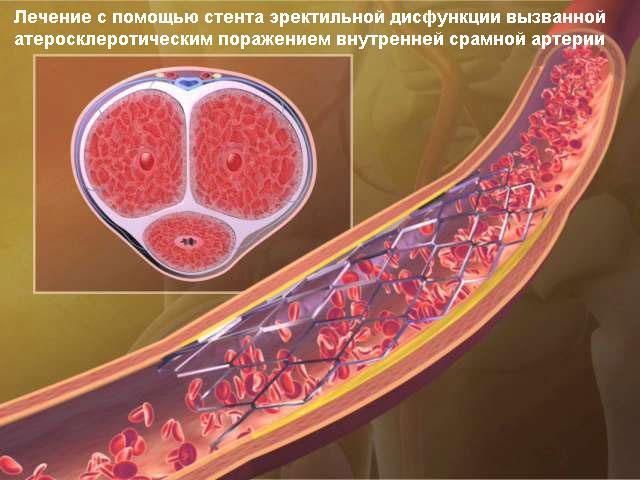

После физической и психоэмоциональной стимуляции нервы посылают сигнал к СОСУДИСТОЙ системе, что значительно увеличивает приток крови к половому члену. Две артерии несут кровь в кавернозные тела полового члена и после кровенаполнения и увеличения давления в кавернозных телах полового члена происходит эрекция.

В 80% случаев причина носит СОСУДИСТЫЙ характер. Как было объяснено выше, в случае нарушения притока крови к половому члену, НАСТУПАЕТ ЭРЕКТИЛЬНАЯ ДИСФУНКЦИЯ. Основной причиной снижения притока крови служит сужение просвета приводящих артерии в результате атеросклеротического процесса в стенке артерии.

Мы исходим из фундаментального правила – устранить причину, а не лечить косвенным путем, как, например, действуют общеизвестные лекарства Виагра или Сиалис. В нашей клинике мы предлагаем современную и высококвалифицированную диагностику сосудистой системы таза и гениталий и, в случае наличия показаний (сужения или закупорки артерии), мы устраняем эту причину с помощью малоинвазивного (без хирургической операции) лечения – расширения суженных артерии и их внутрипросветного протезирования.

После прокола артерии на бедре, в просвет сосуда вводится специальный зонд катетер, который подводится прицельно к артериям, кровоснабжающим половой член. После диагностики артерии и обнаружения сужения, в зону поражения артерии подводится миниатюрный баллонный катетер и сужение устраняется после раздувания баллончика. После сдувания и удаления баллона, на месте расширенного участка артерии ставится специальный каркас, который закрепляет результат и удерживает просвет артерии в раскрытом состоянии, нормализуя таким образом кровоток через расширенный и протезированный участок артерии. Указанная операция делается без общего наркоза и разрезов, только под местной анестезией с помощью маленького прокола (2-3мм) в бедренной артерии. В результате такого неинвазивного вмешательства нормализуется кровоток и, соответственно, нивелируется сосудистая причина эректильной дисфункции.